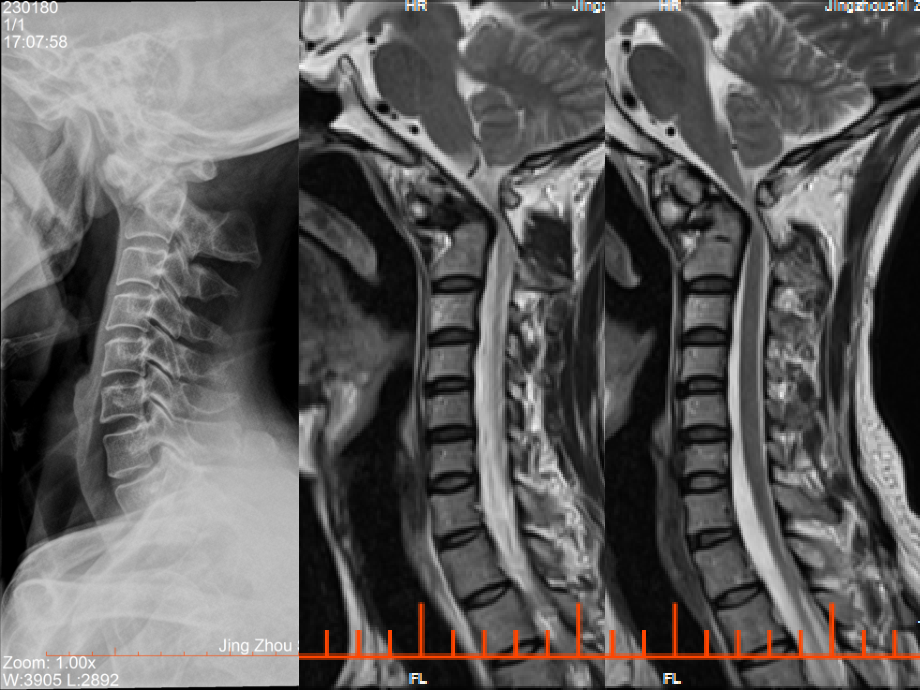

单击此处编辑母版标题样式,单击此处编辑母版文本样式,第二级,第三级,第四级,第五级,*,*,*,病例6,M 41y 右侧肢体不适半年,加重伴乏力2月,患者半年前无明显诱因出现右侧肢体不适,无明显乏力,2月前从高处摔下,头部着地、昏迷,5min后苏醒,自觉四肢麻木,行动不力,查CT颅脑未见异常。,结论:颅颈交界区畸形,颅颈交界区畸形,包括颅底凹陷症、扁平颅底、小脑扁桃体下疝畸形、颈椎融合、寰枕融合、寰枢椎脱位等。以前三种多见。,颅底凹陷症临床症状,患者可有颈短、发际低、颅形不正、面颊耳郭不对称,但无明显神经系统症状。,1.上颈神经根刺激症状:,枕部慢性疼痛,颈部活动受限,感觉减退,一侧或双侧上肢麻木、疼痛、肌肉萎缩、强迫头位等。,2.后组脑神经障碍症状:,吞咽困难、呛咳、声音嘶哑、舌肌萎缩、言语不清、咽反射减弱等球麻痹的症状,以及面部感觉减退、听力下降、角膜反射减弱等,3,.延髓及上颈髓受压体征:,四肢无力,感觉障碍,锥体束征阳性,尿潴留,吞咽、呼吸困难,手指精细动作障碍,位置觉消失等,4.小脑功能障碍,5.椎动脉供血障碍,6.颅内压增高症状,颅底陷入的测量线,枕鄂线,(Chamberlain线):硬腭后缘-枕骨大孔后缘,齿状突高于此线3mm为颅底陷入。,基底线,(Mc Gregof线)硬腭后缘-枕骨最低点,齿状突高于此线6mm为颅底陷入。,BULL角,:侧位片上,硬腭平面与寰椎平面的夹角,大于13为颅底陷入。,Fidhgold线,:正位片上两侧二腹肌沟连线,齿状突距此线小于10mm;或两侧乳突尖连线,齿状突高于此线2mm为颅底陷入。,Boogard角,:枕骨大孔前后缘连线与斜坡的夹角,大于130为颅底陷入。,Klous高度指数,:侧位片上鞍结节-枕内粗隆连线,齿状突距此线小于40mm为颅底陷入。,外耳孔高度指数,:侧位片上由外耳孔中心点到枕大孔前后缘连线的垂直距离,正常值为13-25mm,小于13mm为颅底陷入。,延髓、上段颈髓轴线夹角,:小于130为颅底陷入。,扁平颅底,颅底角,:前颅底与斜坡之间的夹角,正常时120-140。大于正常值为扁平颅底。,小脑扁桃体下疝畸形,Chiari畸形:指小脑下部或同时有脑干下部和第四脑室之畸形,向下作舌形凸出,并越过枕骨大孔嵌入椎管内。,Chiari畸形定性诊断,小脑扁桃体尖部到枕骨大孔连线间距5mm;3-5mm为可疑。,Chiari畸形分型:I型,分四型:,Chiari畸形分型:II型,Chiari畸形分型:III型,Chiari畸形分型:IV型,颈椎融合、寰枕融合、寰枢椎脱位,颈椎体融合:Klippel-Feil综合征,,为两个或两个以上颈椎融合性畸形,表现为颈椎数目减少,颈项缩短,头颈部运动受限。需要注意的是,中低位颈椎融合引起的短颈畸形,,其临床特点是创伤轻、症状重,可造成四肢瘫痪,而X线检查又不表现出明显的骨损伤征象。,寰枕融合,在胚胎发育过程中,寰椎与枕骨分裂不全即导致寰枕融合。在MR矢状位上通常不能显示寰椎后弓,或仅见枕骨大孔后缘与一小骨块相连。完全相连或部分相连均有相对应的表现。,MR能显示颈延髓交界处受压、变细、软化的范围和程度以及可能伴发的小脑扁桃体疝。,寰枢椎半脱位,寰枢椎半脱位:枢椎齿状突与寰锥前弓间距儿童不超过4mm,成人2.5-4mm。,枢椎齿状突,枢椎有两个原发骨化中心,出生时多已融合。齿状突尖部在2-4岁时出现继发骨化中心,12岁时齿状突与枢椎融合,如不融合,则成为游离骨组织,称为终末骨。,参考链接,